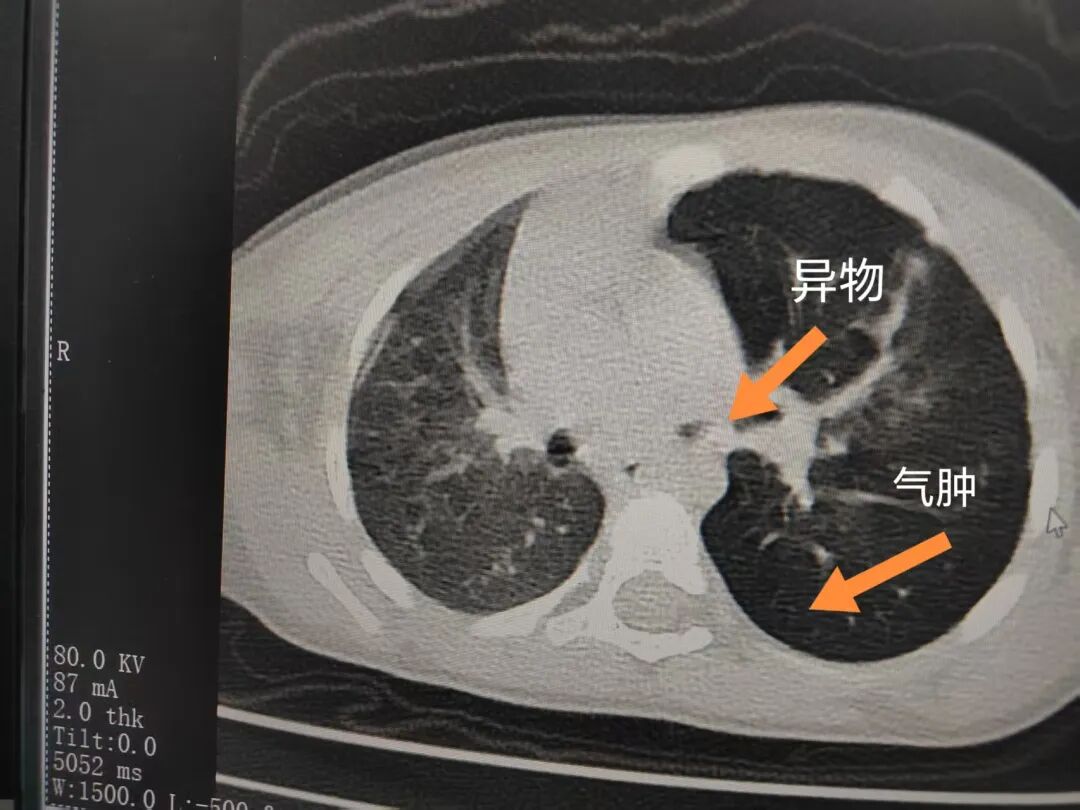

三天后(11月13日),趙寶出現高熱、咳喘加重,家長著急了,再次帶他來到醫(yī)院。CT檢查顯示左肺過度充氣,左肺上下葉支氣管主干見不規(guī)則高密度影,左肺上葉可見大片狀密度增高影,縱隔窗實變,提示為“左側支氣管內異物并繼發(fā)性改變,左肺上葉舌段肺膨脹不全”。

市二院小兒呼吸內科團隊迅速為患兒制定了周密的手術方案,并很快安排了氣管鏡探查。術中,主治醫(yī)師田慧等憑借嫻熟的氣管鏡操作技術成功將異物大塊板栗取出。由于板栗在氣管內存留時間較長,質地軟糯易碎,大大增加了手術難度。檢查還發(fā)現,異物停留部位的氣管黏膜已出現充血紅腫、糜爛,導致患兒住院時間相應延長。此次事件給趙寶的家庭帶來了不小的驚嚇與擔憂,也再次為廣大家長敲響了警鐘。